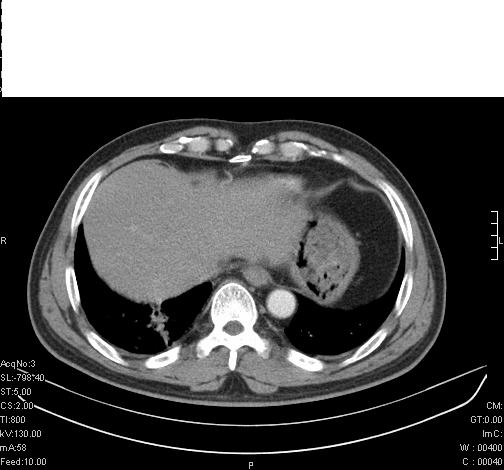

标题: CT6685:右肺阻塞性炎症,增强CT。

前几天,发了患者的平扫片,患者抗炎一周后增强扫描。右中叶病灶吸收明显,但下叶病灶未见明显吸收。右肺门可见结节影,看来凶多吉少

右肺下叶支气管管腔狭窄,管壁增厚,右下肺见斑片状高密度影,考虑右侧肺门中心肺癌伴阻塞性肺炎

右肺下叶支气管壁不规则增厚,右肺下叶有斑片状影分布。考虑右肺中央型肺癌伴右肺下叶阻塞性改变。建议支纤镜检查。平扫比增强较好显示了病变情况。

既然抗炎治疗有效,可继续治疗;右肺下叶支气管管腔狭窄,管壁增厚,右下肺见斑片状高密度影,右侧主支气管后见结节影(淋巴结?),肺癌不能排出。